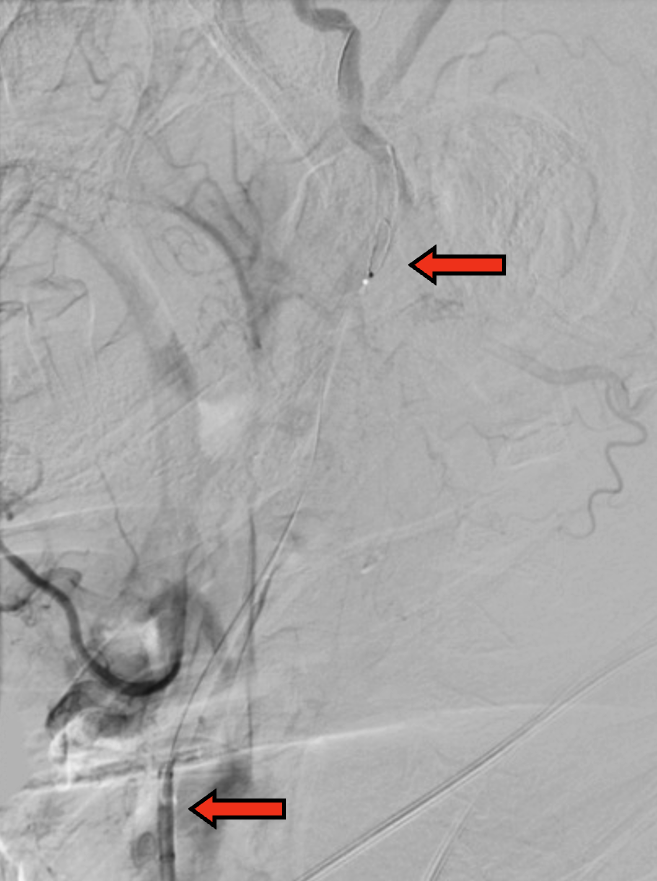

路图引导下,BGC置于颈总动脉,病变近端充盈球囊

球囊充盈后,手推造影,造影剂滞留能进一步明确狭窄病变特征。开放阀门(stopcock),可见造影剂回流,提示反向血流建立

图1. 当BGC工作时,颈总动脉、颈内动脉、颈外动脉、Willis环中颈内动脉的血流方向示意图。(注:箭头代表血流方向)